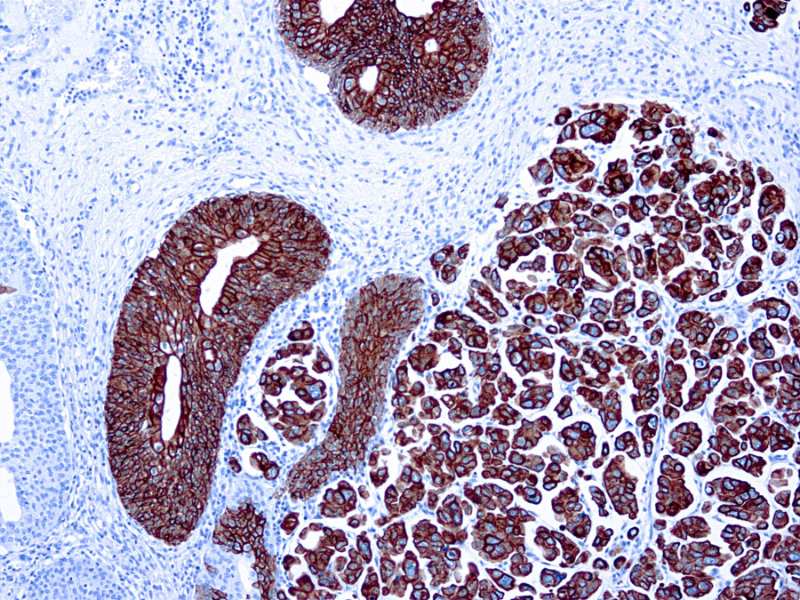

Cytokeratin 7 rmab 063 carincoma Published January 24, 2021 at 800 × 600 in Cytokeratin 7 rmab 063 carincoma Cytokeratin 7 rmab 063 carincoma Cytokeratin 7 rmab 063 carincoma ← Previous Next →